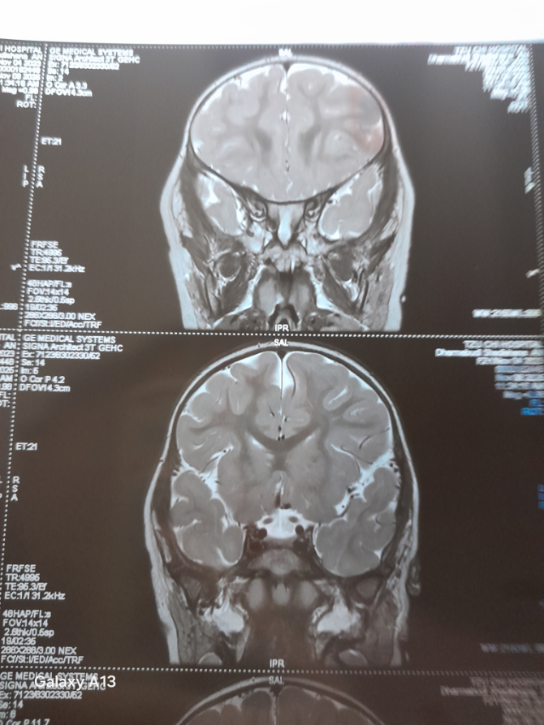

Selama di sini, Hana sudah dan masih menjalani berbagai pemeriksaan secara bertahap, seperti rontgen (X-ray) dan tes Mantoux, cek darah dan urine, USG ginjal dan hati, MRI 3T dengan kontras, serta CT scan.

Hana akan menjalani operasi sklerosis hipokampus untuk mengatasi kejang yang sudah tidak terkendali. Berdasarkan hasil MRI, ditemukan banyak sumber kejang pada otaknya.

Hana juga mengalami penyusutan pada otak kiri serta terdapat cairan abnormal di bagian otaknya.

Dari hasil MRI terbaru Hana di Malaysia, memang benar Hana didiagnosis sklerosis hipokampus kiri. Tapi karena ukurannya masih sangat kecil, untuk sekarang belum bisa dilakukan tindakan apapun, termasuk operasi otak.